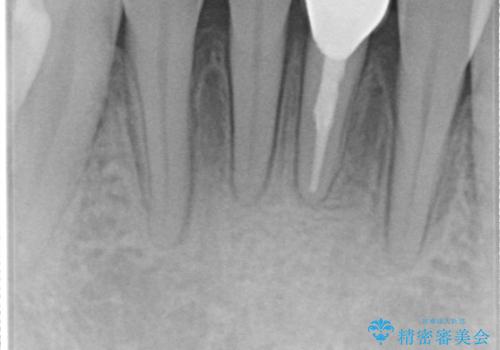

根管治療を行なったのちオールセラミッククラウン(スタンダード)にて修復治療を行なっております。

歯髄壊死により変色した歯は根管治療が必要となります。

根管治療の注意事項(リスク・副作用など)

- 根管治療により類似の全ての症例の問題が解決するわけではなく、症例はあくまでも一例です

- 根管治療により痛みや腫れがひかない事や、術後に痛みや腫れが生じる事、治療によるファイル破折やパーフォレーションなどの偶発症、術後の歯根破折を生じる可能性もあります